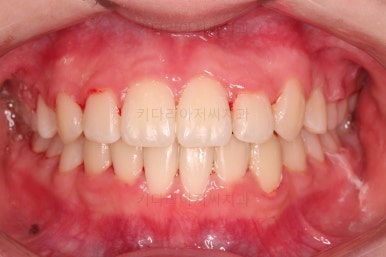

부산교정치료 초진 시 입안의 모습입니다.

치아가 전반적으로 삐뚤고, 덧니가 두드러져 보이네요.

그리고 선을 그려놨는데 윗니의 라인과 아랫니의 라인이 평행이 아니죠.

기울어 있어서 양측의 교합의 강도가 다른 상황이었습니다.